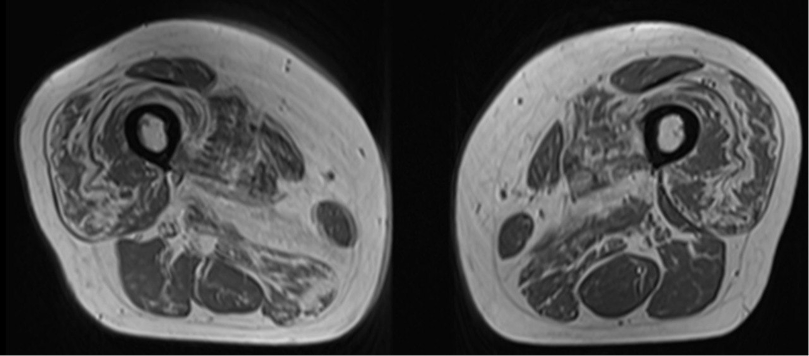

МРТ мышц бедер и голеней (Посмотреть рисунок): отмечается избирательное поражение мышц передней и медиальной групп бедра.

МРТ мышц (аксиальные срезы!) может играть важную роль в диагностике:

- могут быть признаки отека мышц

- преимущественное поражение и выраженная атрофия передней группы мышц бедра, при более сохранной задней группе

- признак «ундулирующей/ волнообразной мембраны» (встречается в 75% случаев IBM), см рис. ниже. (https://t.me/significogene/3620)

МРТ мышц бедер и голеней